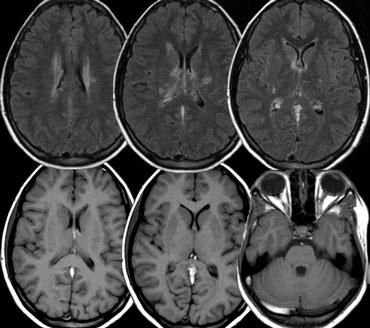

PRES

PRES là viết tắt của Hội chứng Bệnh não Sau có Hồi phục (Posterior Reversible Encephalopathy Syndrome).

Hội chứng này còn được gọi là Hội chứng Bệnh chất trắng Sau có Hồi phục [RPLS].

Biểu hiện điển hình là tình trạng phù não do cơ chế vận mạch (vasogenic edema) có khả năng hồi phục, phân bố trong vùng tưới máu của tuần hoàn sau, tuy nhiên các cấu trúc thuộc tuần hoàn trước cũng có thể bị ảnh hưởng (6).

Nhiều nguyên nhân đã được ghi nhận, bao gồm tăng huyết áp, sản giật và tiền sản giật, các thuốc ức chế miễn dịch như cyclosporine.

Cơ chế bệnh sinh chưa được hiểu rõ hoàn toàn, nhưng được cho là liên quan đến tình trạng tăng tưới máu não, dẫn đến phá vỡ hàng rào máu-não, thoát mạch của dịch có thể chứa máu hoặc các đại phân tử, và gây ra phù não vỏ hoặc dưới vỏ.

Hình ảnh điển hình của PRES biểu hiện rõ nhất dưới dạng tăng tín hiệu trên chuỗi xung FLAIR tại vùng vỏ não và chất trắng dưới vỏ vùng đỉnh-chẩm và trán sau; ít gặp hơn là tổn thương tại thân não, hạch nền và tiểu não.

Hình ảnh bên trái là của một bệnh nhân có các triệu chứng thần kinh hồi phục được.

Các bất thường được ghi nhận cả ở vùng tuần hoàn sau lẫn tại hạch nền.

Tiếp tục.

Bốn ngày sau, hầu hết các bất thường đã biến mất.